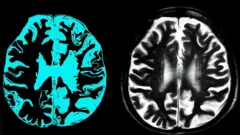

Деменция

Ученые: изменения в мозге при менопаузе напоминают те, что происходят при болезни Альцгеймера

Можно ли победить болезнь Альцгеймера? Ученые считают, что сделают это через 5-10 лет